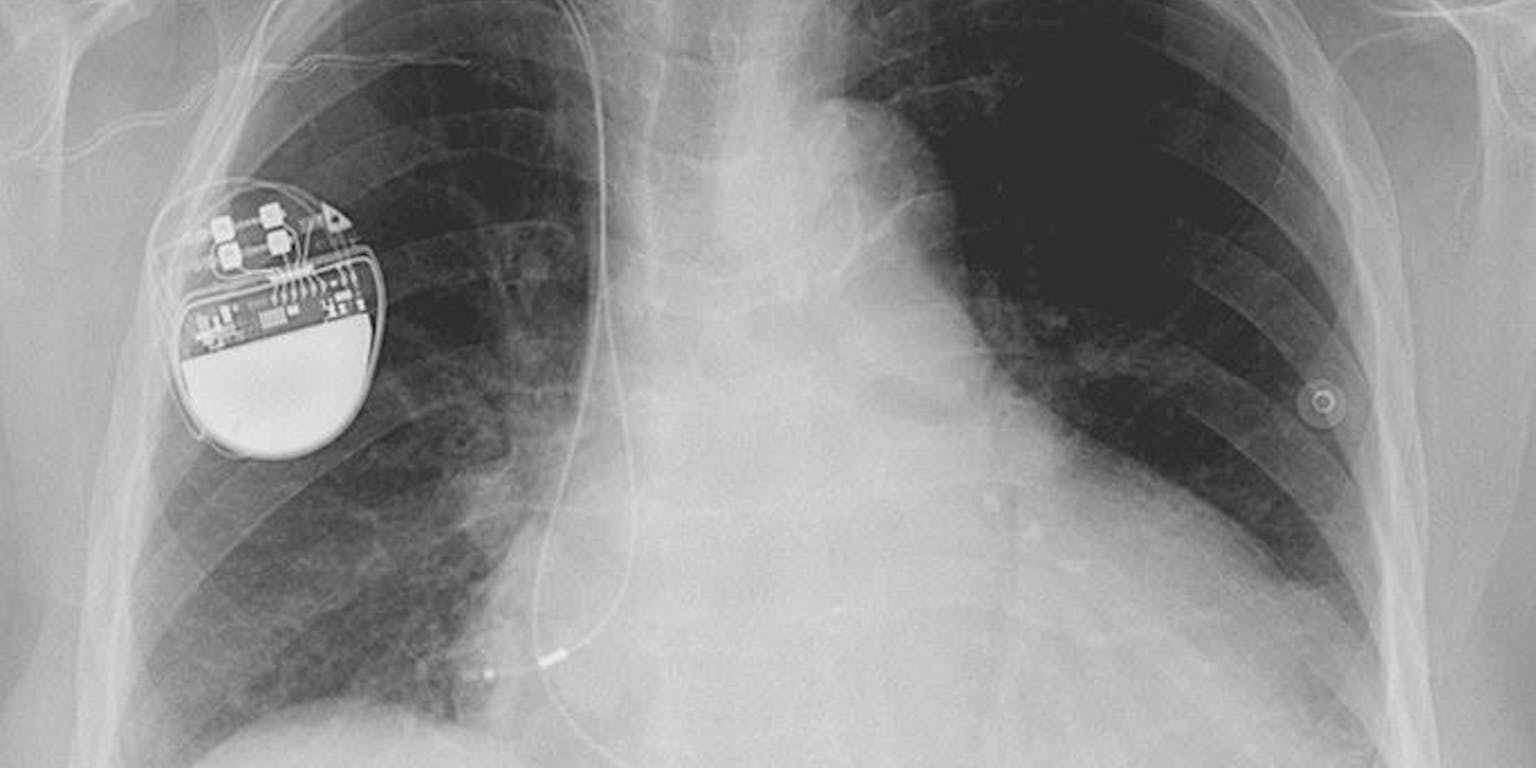

In toenemende mate maken mensen gebruik van elektrische implantaten. Denk aan pacemakers die het hart kunnen ondersteunen, of gehoorapparaten. De energie voor die apparaten komt momenteel meestal uit lithium-jood-batterijen. Deze moeten goed ingepakt worden. De stoffen in zo’n batterij mogen namelijk niet in het lichaam vrijkomen. Maar naarmate implantaten steeds kleiner worden, neemt zo’n robuust omhulsel relatief steeds meer ruimte in.

Deze brandstofcel zou volgens de wetenschappers toepassingen kunnen krijgen als energiebron voor implantaten zoals pacemakers.